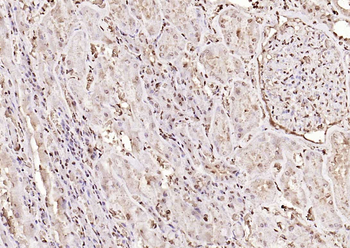

100 μl, 50 μl, 200 μl - HSC70 Mouse Monoclonal Antibody [orb704174]Featured

IF, IHC-Fr, IHC-P, WB

Human, Mouse, Rat

Mouse, Rat

Mouse

Monoclonal

Unconjugated

100 μl, 50 μl, 200 μl - ATF4 Recombinant Rabbit Monoclonal Antibody [orb704304]Featured